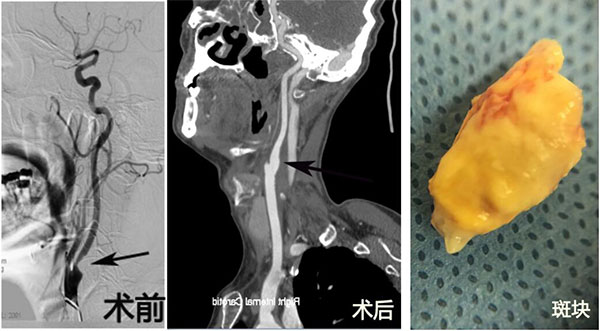

病例A 男,72岁。右侧颈内动脉狭窄

颈动脉狭窄是导致缺血性脑卒中常见的原因,颈动脉狭窄内膜剥脱手术(CEA)是治疗颈动脉狭窄的金标准。在美国每年有超过20万人接受CEA手术,而在我国每年不足2000人,且主要集中在北方地区,CEA的开展具有广阔的前景。近年来,CEA手术在全国已呈现出星火燎原之势,越来越多的医院逐渐开展了此项技术,越来越多的患者正逐渐接受CEA手术。与颈动脉支架相比,能直接切除动脉内的粥样硬化斑块是其明显的优势。除此之外,CEA具有可节省较多的费用、、术后无需严格大量的服用抗血小板药物、围手术期缺血事件的发生及再狭窄率低等优点。此项技术的成功开展,进一步丰富了我院颈动脉狭窄患者的治疗选择,也必将造福于华南地区更多的患者。